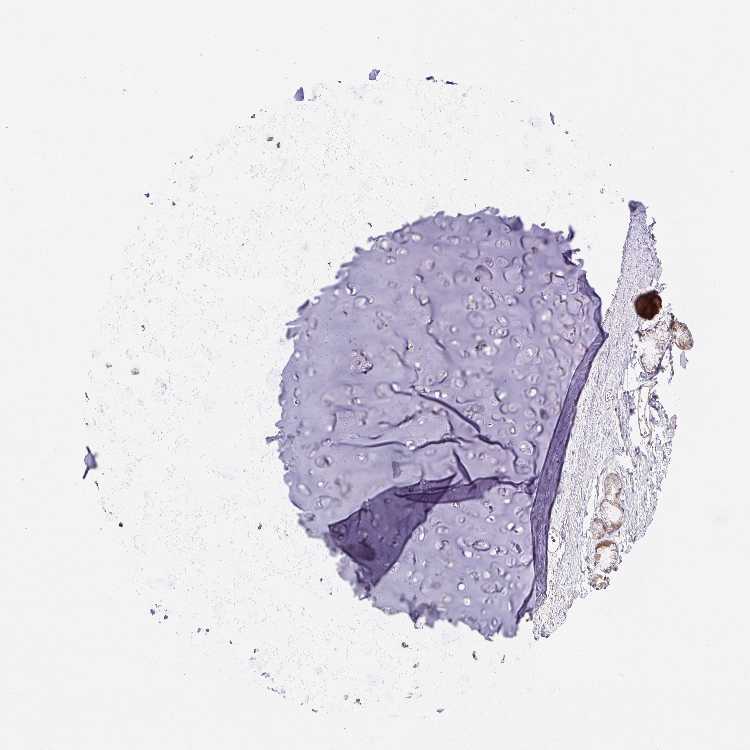

SOFT TISSUE 1 - Antibody stainingi

Antibody staining in the annotated cell types in the current human tissue is reported as not detected, low, medium, or high, based on conventional immunohistochemistry profiling in selected tissues. This score is based on the combination of the staining intensity and fraction of stained cells.

Each image is clickable and will lead to virtual microscopy that enables deeper exploration of all samples and also displays staining intensity scores, fraction scores and subcellular localization as well as patient and tissue information for each sample.

Antibody HPA057489

Chondrocytes Not detected

Fibroblasts Not detected

SOFT TISSUE 2 - Antibody stainingi

Peripheral nerve Not detected